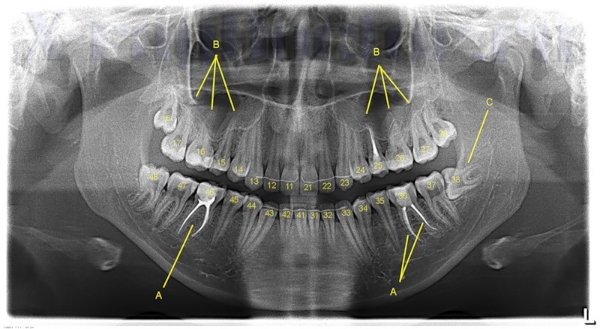

Ортопантомография (ОПТГ)

ортопантомографияПрименяется в стоматологии, практике ЛОР-заболеваний, хирургии челюстно-лицевого отдела черепа, а также в косметологии. Как и во всех диагностических методах, использующих рентген, в ортопантомографии наблюдается тенденция перехода с пленочного варианта на цифровой формат.

Преимущества компьютерной ОПТГ:

• снижение дозы радиационного излучения;

• получение более качественной картинки;

• возможность вывода изображения на монитор;

• создание архива в электронном виде.

Показания:

• кариес;

• периодонтит;

• травмы костей черепа;

• воспалительные процессы в черепных пазухах;

• периостит;

• мониторинг динамики стоматологического лечения.

ОПТГ способствует установке и уточнению диагноза, помогает контролировать ход лечения.

Рентгенологические методы диагностики активно используются в стоматологии. Без рентгена сложно себе представить стоматологическое лечение высокой и средней степени сложности. Патологии костей черепа и воспалительные процессы мягких тканей также являются показанием для назначения данного способа диагностики.